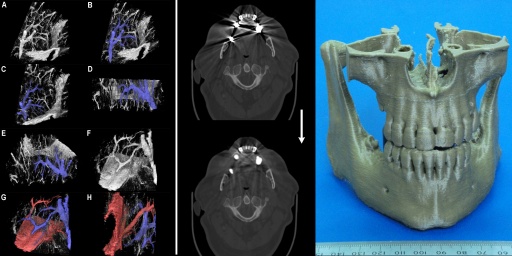

We develop custom advanced algorithms and write our own software to provide truly unique services for cutting edge medical research. Some of our techniques are illustrated above: (Left) Virtual dye casting, (Middle) Metal artefact reduction in CT scans, (Right) 3D printed models derived from a patient's CT imaging. Some details are given below:

- 3D Printed Anatomical Models from Patients' CT Scans - We have developed specialist software and techniques to make high quality clinical grade 3D printed models of a patient's bony anatomy from their CT scans. An example of our physical 3D printed models is shown in the above figure (right) and a YouTube video showing some our models can be viewed here: 3D model video demo. Such models are dimensionally accurate (our quality control procedure ensures that concordance between the physical model and the calibrated CT scan is better than 1 mm). This allows our models to be used for surgical planning, pre-bending titanium plates, medical education, surgical training, etc. Please note: Our models must NOT be used for internal purposes (i.e. any use that puts the model in contact with live patient tissue is prohibited). Thus our models must not be used as implants or intra-operative cutting guides. Below are some examples of the virutal models made from CT scans of a maxilla and a mandible from separate patients.

- Metal Artefact Reduction in CT Scans - We have considerable experience of head and neck work and our 3D modelling processes in this region need to recover high fidelity profiles of bony structures of the jaws. Unfortunately many people have extensive metalwork in their teeth (amalgam fillings, crowns, etc.) which cause severe distortions in CT images due to over-scattering and lack of transmittance of the X-ray beams in the scanner. This results in gross distortions of the reconstructed images (an example is shown in the image at the top of this page - middle, top - and also in the figure below, left). Although many algorithms to reduce such artefact have been published since the mid 1980's we found none of them met out specific needs for reduction of severe (as opposed to only moderate) dental artefacts or others were made for use with specific scanners or required access to the raw scanner data. We rarely get access to raw CT scanner data and we use CT images from a variety of sources supplied to us by our clients. For this reason we developed our own in-house algorithm specially designed to deal with severe dental metalwork-induced artifacts. This is a non-iterative algorithm based on non-linear interpolation and inspired by the Kriging technique used in geosurveying. We call this the MARCI™ algorithm (Metal Artefact Reduction by Constrained Imputation). An example result of applying our MARCI algorithm is shown in the image at the top of this page (middle, bottom) and in the figure below (right). No algorithm can completely remove such severe artefact but our method reveals sufficient hidden detail for us to make good quality 3D models even from severely degraded images. Please note: We do not report CT scans or other radiology studies - we only process images as a service. MARCI algorithm processing is made available for research purposes only because it does not have any regulatory approval for clinical use. Below is a close-up of soft tissue windows from an original CT scan with severe metal artefacts (left) and the result of our MARCI algorithm on the same scan (right) showing not only reduced distortion of the bone profiles (which is what the algorithm was primarily designed for) but the added bonus of increased visibility of soft tissue structures as well.